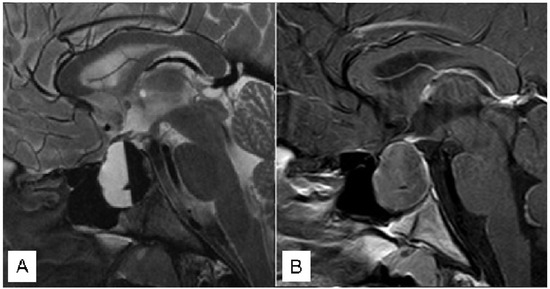

3.1.1. Case 1

3.1.2. Case 2

3.1.3. Case 3